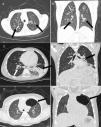

ResultadosA amostra do estudo consistiu em 86 pacientes (sexo feminino, n = 47; 54,7%), com média de 66 meses (IIQ, 16‐147). A maioria tinha entre dois e oito anos (34,8%) ou ≤ 1 ano (29%) (tabela 1). Apenas três doenças foram identificadas neste estudo. A fibrose cística (FC) foi diagnosticada em 44 (51,2%) (fig. 1A and B), bronquiolite obliterante (BO) em 27 (31,4%) (fig. 1C and D) e a CPAM em 15 pacientes (17,4%) (fig. 1E and F). Todos os indivíduos com suspeita de CPAM foram submetidos à angio‐TC, sequestro pulmonar concomitante foi diagnosticado em dois (15,3%) casos.

Paciente do sexo masculino, oito anos. Imagens de TC axial (A) e coronal (B) com ultrabaixa dose demonstraram bronquiectasias cilíndricas (centrais) peri‐hilares (setas), sugestivas de fibrose cística. Imagens de TC axial (C) e coronal (D) com ultrabaixa dose mostram um caso de uma criança do sexo masculino de três anos com espessamento da parede brônquica (seta branca) e atelectasia no lobo inferior esquerdo (seta preta), sugestivo de bronquiolite obliterante. Imagens de TC axial (E) e coronal (F) com ultrabaixa dose demonstraram malformação congênita pulmonar das vias aéreas de tipo I no lobo superior esquerdo (seta) – Malformação adenomatoide cística pulmonar – em uma criança do sexo feminino de cinco anos.